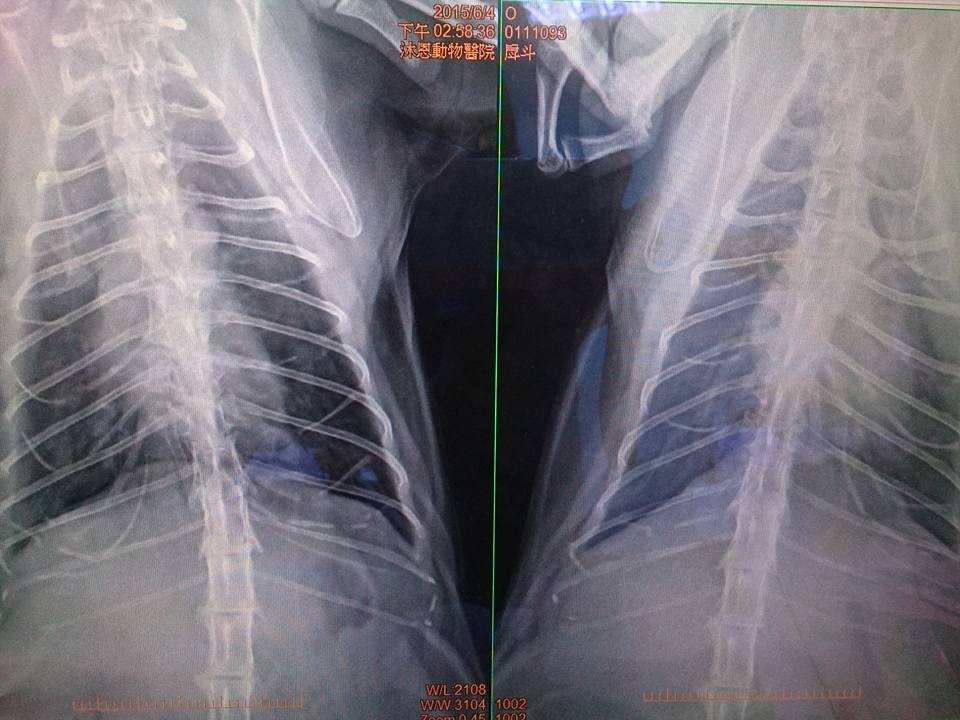

2015/4月厚道食慾胃口下降,就醫檢查發現肝指數較高,超音波無明顯異狀,X光片肺部較多白影處,可能上呼吸道感染,或者是剛救援時感染肺炎的後遺症,給予口服抗生素,因為厚道的牙齒所剩無幾,又口炎需要噴口樂減緩不舒服,因為肝指數偏高每天需要打皮下點滴75CC補充水分,治療後食慾慢慢恢復,五月追蹤肺部狀況進行X檢查,發現心臟旁稍有異樣,建議要轉院進行心臟超音波檢查,約診心臟專科專心動物醫院進行詳細檢查,檢查結果稍微心室肥厚,可能先天就這樣,也不一定會惡化,需半年回診監控情況,最久一年一定要回診掃心超,目前不需吃藥,持續每天打75ml,專心掃描心臟超音波的費用還請各位幫忙。